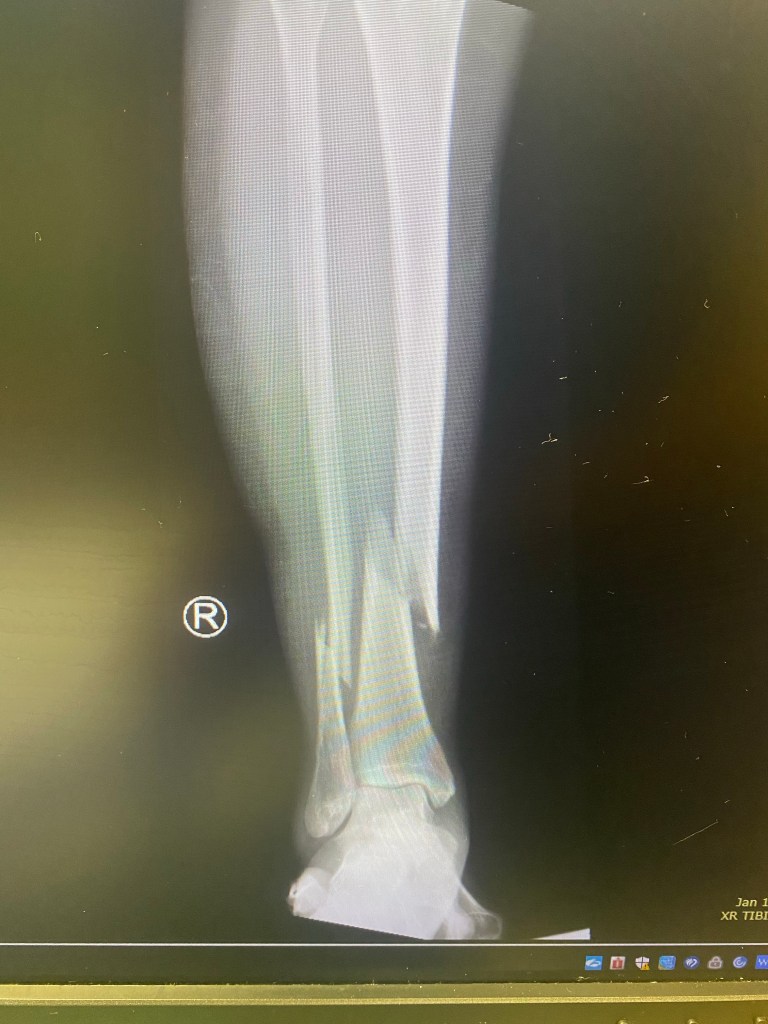

The sun was going down and the temperature had quickly dropped to freezing. Rushing, I lofted into the air. The roots of the moss under my feet tore. Beneath it was very slippery mud and the incline of the hill was steep. The full break was immediately evident! It was actually two bones snapped in two which was loudly audible. My leg was literally a C shape.

Three counties of sweet medics pooled physical resources to help me get to the hospital via ambulance. They had to load me in a type of stretcher that they could manage in the mud a s then transfer me to an ambulance. I was treated so nicely. They administered fentanyl for the excruciating pain. Necessary manhandling was followed by more of the same in ER. The doctors were fantastic and got x rays and a CT scan to assess the reality of the situation. being moved was the highest degree of pain I have ever felt however. My sister and brother in law came to see me there.

For the surgery they gave me two nerve blockers for the pain of the procedure. Six pins and a rod were inserted from above my knee since the bones were in half. My surgeon monitored the leg from an X-ray during the surgery. I was on non weight bearing for a month and a half. The last month of that I was in a nursing home.